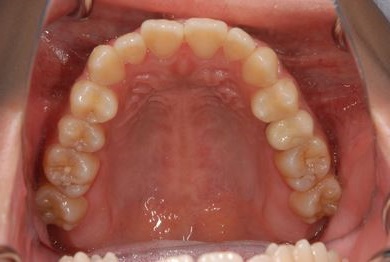

治療後

• 治療後